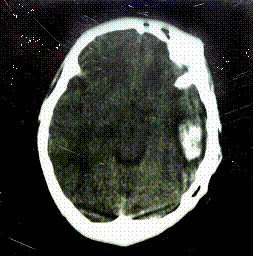

3.腦轉移 常繼發於肺轉移之後,是死亡的主要原因,在最早期,是腦動脈內瘤栓期,造成局部缺血,出現一過性症狀,如腿軟跌倒、失語、失明,經幾秒鐘或幾分鐘後即恢復。以後在小動脈內形成動脈瘤,繼續生長發展,產生破壞性症狀,造成蛛網膜下腔及附近腦組織出血,主要的症狀為頭痛、偏癱、嘔吐、平衡失調、視覺障礙、失語、高熱、抽搐,以至昏迷,如引起腦疝,病人可突然死亡。

(三)疑有腦轉移時,可作CT、B超檢查,可顯示轉移灶,但病灶小時,不一定能明確診斷,可作腦脊液與血漿的hCG測定,腦脊液hCG水平:血漿hCG水平>1:60,則示有hCG直接泌入腦脊液,即可診斷為腦轉移。